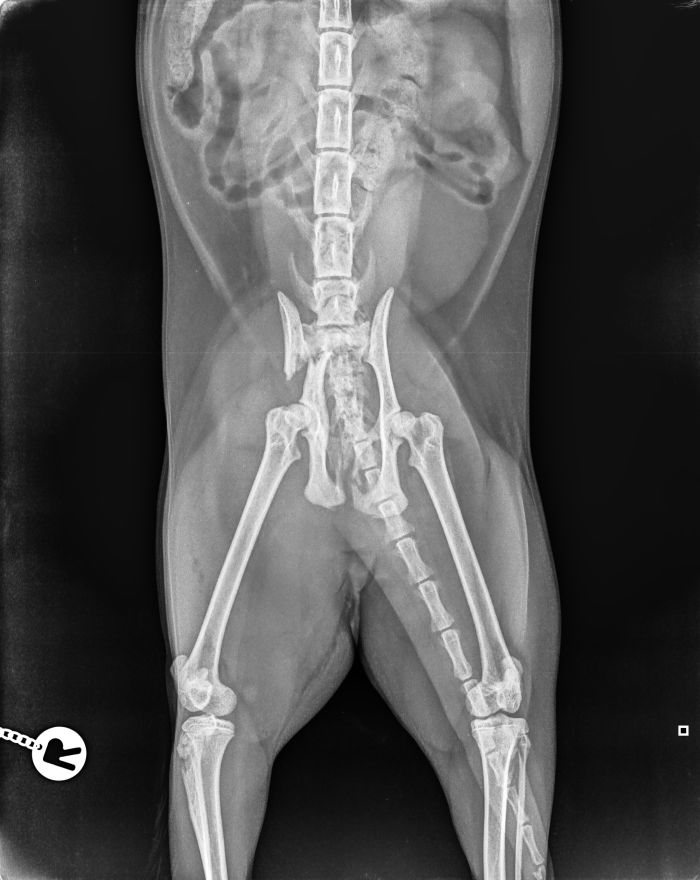

Schraubenstabilisierung von Frakturen

Bei der "Schraubenfixation" wird auf Platten verzichtet. jedoch wird diese Methode der Frakturbehandlung nur in seltenen Fällen verwendet. Dies wäre z.B. zur Fixation im Beckenbereich oder bei Bandansatzausrißen möglich.